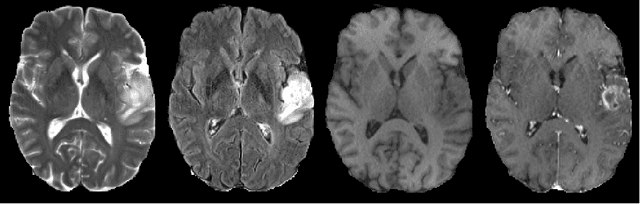

Abstract:In this work, we investigate the value of uncertainty modeling in 3D super-resolution with convolutional neural networks (CNNs). Deep learning has shown success in a plethora of medical image transformation problems, such as super-resolution (SR) and image synthesis. However, the highly ill-posed nature of such problems results in inevitable ambiguity in the learning of networks. We propose to account for intrinsic uncertainty through a per-patch heteroscedastic noise model and for parameter uncertainty through approximate Bayesian inference in the form of variational dropout. We show that the combined benefits of both lead to the state-of-the-art performance SR of diffusion MR brain images in terms of errors compared to ground truth. We further show that the reduced error scores produce tangible benefits in downstream tractography. In addition, the probabilistic nature of the methods naturally confers a mechanism to quantify uncertainty over the super-resolved output. We demonstrate through experiments on both healthy and pathological brains the potential utility of such an uncertainty measure in the risk assessment of the super-resolved images for subsequent clinical use.